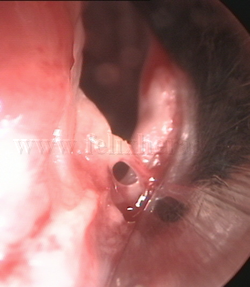

Cuerpo

extraño endobronquial |